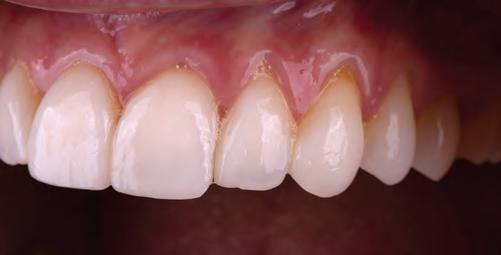

A 31-year-old woman presented with cosmetic concerns regarding her smile and requested a conservative enhancement. After clinical and radiographic analysis, digital 35mm photographs were taken and reviewed by the restorative clinician, technician, and surgeon (Fig 1). A digital impression was taken of the maxillary and mandibular arches using an intraoral scanner (Trios 3, 3Shape; Fig 2), and a smile design was developed with NemoSmile Design 3D software (Nemotec; Fig 3a). This allows for a facially driven smile frame to be created using reference lines of facial and smile proportions and natural teeth shapes and textures from the digital library (Fig 3b).

After developing the simulated mock-up, a 3D-printed resin model was created using CAD software (Fig 4a), and a clear PVS matrix (Exaclear, GC America) was fabricated to replicate the printed diagnostic wax-up using a nonperforated tray (Fig

Fig 1 Preoperative clinical views of a 31-year-old woman presenting with diastemas and limited tooth visibility. (top) Portrait. (center row) Intraoral views. (bottom row) Smile.

4b). This matrix was used to create an intraoral motivational mock-up with bis-acryl composite (Luxatemp Ultra, DMG). This additive mock-up provides the interdisciplinary team with an intraoral translation for evaluation (Fig 5). Upon evaluation of the digital smile frame and the clinical translation, it was determined that multiple esthetic and restorative requirements were necessary for an optimal biologic framework, and the interdisciplinary team determined the best sequence for these procedures. The patient was presented with the interdisciplinary treatment possibilities that included restoring the maxillary anterior teeth and premolars with a minimally

invasive preparationless procedure or with less conservative veneer preparations. The restorative materials discussed included injectable resin composites and ceramic (ie, feldspathic, pressable, machinable). For an optimal biologic framework and health, it was determined that connective tissue grafting would be necessary for treatment of the recessiontype defects on the maxillary left central and lateral incisors, canine, and premolars. The patient opted for the conservative preparationless composite veneers using the injectable resin technique followed by a connective tissue surgical procedure using the tunneling technique.